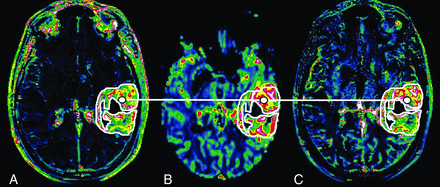

For each tumor, ROIs were manually drawn on Ktrans maps, including the entire contrast-enhanced region. ROIs were copied to corresponding CBV and Vp maps, and a list of pixel values of the ROIs organized by spatial coordinates was obtained for each map (Ktrans, CBV, and Vp) by using the software package Jim (Version 3.0; Xinapse Systems, West Bergholt, United Kingdom). A 20- to 50-mm2 ROI was manually drawn on the contralateral normal-appearing white matter for each tumor used to normalize CBV and Vp (normalized CBV = CBV / CBV of normal-appearing white matter; and normalized VP = VP / VP of normal-appearing white matter). Figure 3 illustrates an example of manually drawn ROIs around enhancing tumor in Ktrans (Fig 3A), posteriorly copied to CBV (Fig 3B) and Vp (Fig 3C) maps. Values of pixels in the same tumor location were compared in the correlation study.

Ktrans (A), CBV (B), and Vp (C) maps through the center of a grade IV glioma. The white line connects corresponding pixels for the correlation study.